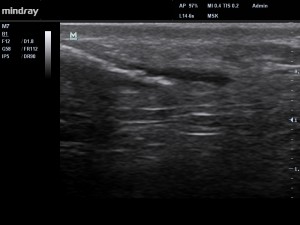

Nous avons réalisé une échographie qui n’a détecté aucune anomalie de son tendon… et pourtant la souffrance du patient est bien réelle. L’échographie nous alors permis de mettre en évidence la présence d’une discrète anomalie en périphérie de son tendon : une para-tendinopathie  !

Fig1. La flèche rouge indique la présence de la paratendinopathie.

Fig2 . Etude comparative des 2 tendons, mettant en évidence la paratendinopathie.

Chez notre patient, l’échographie (Fig 1 – 3 ) montre la présence d’un mécanisme inflammatoire actif, avec présence d’un exsudat au niveau de para-tendon.  On parle précisément d’inflammation fibrineuse dans notre cas. SI la pathologie s’installe dans le temps, la présence de fibrinogène (grosse protéine présente dans le plasma sanguin) va conduire à la prolifération de fibroblastes (petites cellules notamment impliquées dans la fabrication du collagène et certaines protéines du tissu conjonctif ). Le para-tendon va alors s’épaissir, et des adhérences vont se former entre le para-tendon et le tendon, mettant en péril la vascularisation de ce dernier.